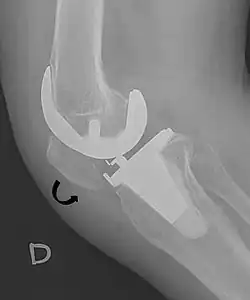

Treatment

For recurrent patellar dislocations or cases with chronic instability, surgical intervention may be necessary. Patella stabilization surgery aims to restore proper kneecap tracking and reduce the risk of future dislocations.[4] Surgical options include reconstruction of the medial patellofemoral ligament (MPFL), realignment procedures such as osteotomy, and soft tissue adjustments around the patella.[4] MPFL reconstruction typically involves harvesting a hamstring tendon, commonly the gracilis, to create a new ligament that is positioned anatomically and secured with suture anchors.[4]

Recovery from patella stabilization surgery typically requires six to eight weeks, during which patients may need to use crutches initially and follow a structured physical therapy program to regain range of motion and strengthen the surrounding musculature.[4]